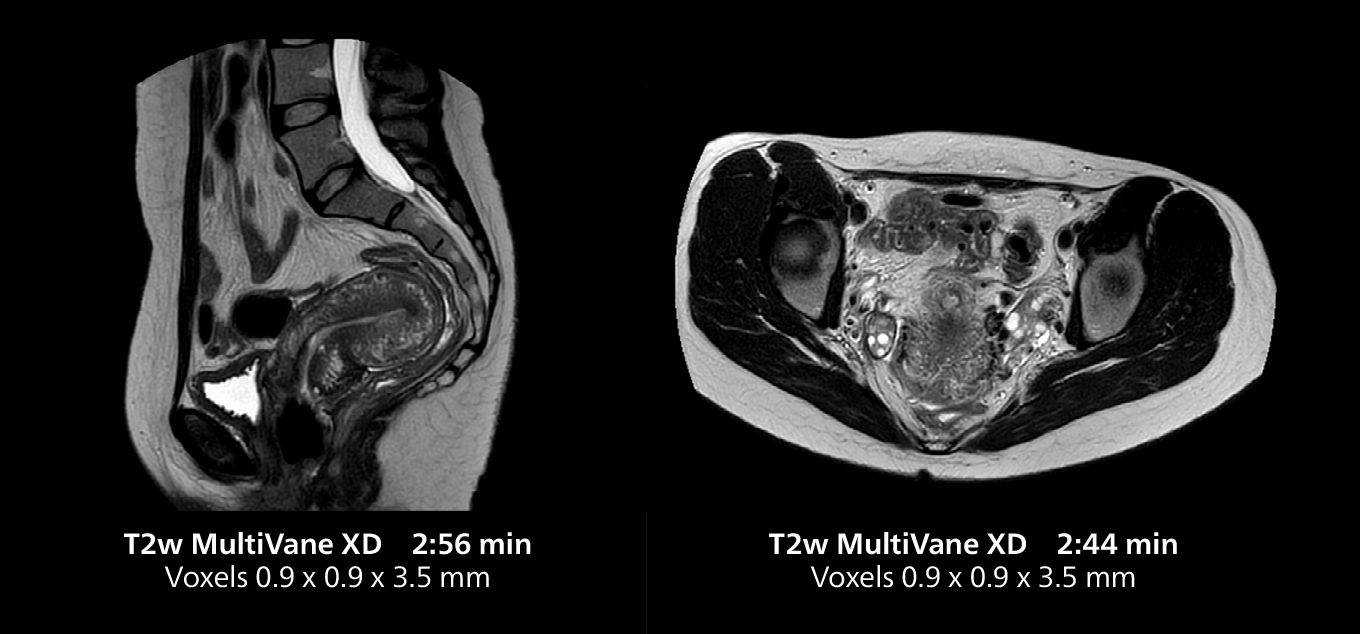

The isotropic high resolution 3D sequence in this MRI case allows for reformatting to obtain other orientations with high quality. Acquired on the MR 5300 system.

“We have more speed in 3D sequences,” Dr. Gellée states. “With Compressed SENSE, we can replace two or three 2D scans withone high-quality 3D scan. High quality additional orientations are then obtained by post-processing of the 3D data set, thus saving scanning time.”

Dr. Gellée often takes advantage of the system’s speed to add more sequences to an exam. “When Compressed SENSE reduces typical exam duration, I can add sequences to increase my confidence in diagnosing. For example, post-gadolinium liver scans used to be axial, but now we can use a faster coronal scan. And because I know that the quality will be good the first time, I know I won’t have to repeat the sequence. That frees up time to comfortably add one more sequence,” she says.